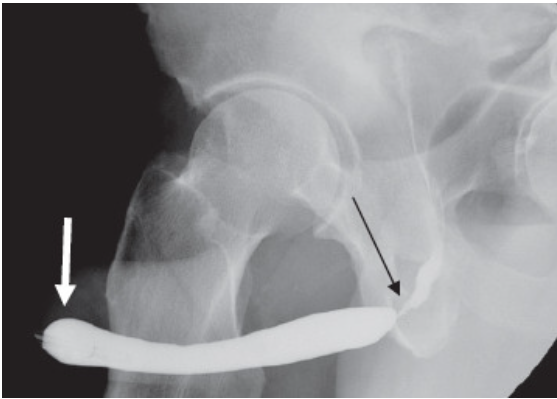

Imagem de Estenose Uretral

Uretrografia mostrando uma estenose severa no segmento da uretra bulbar.